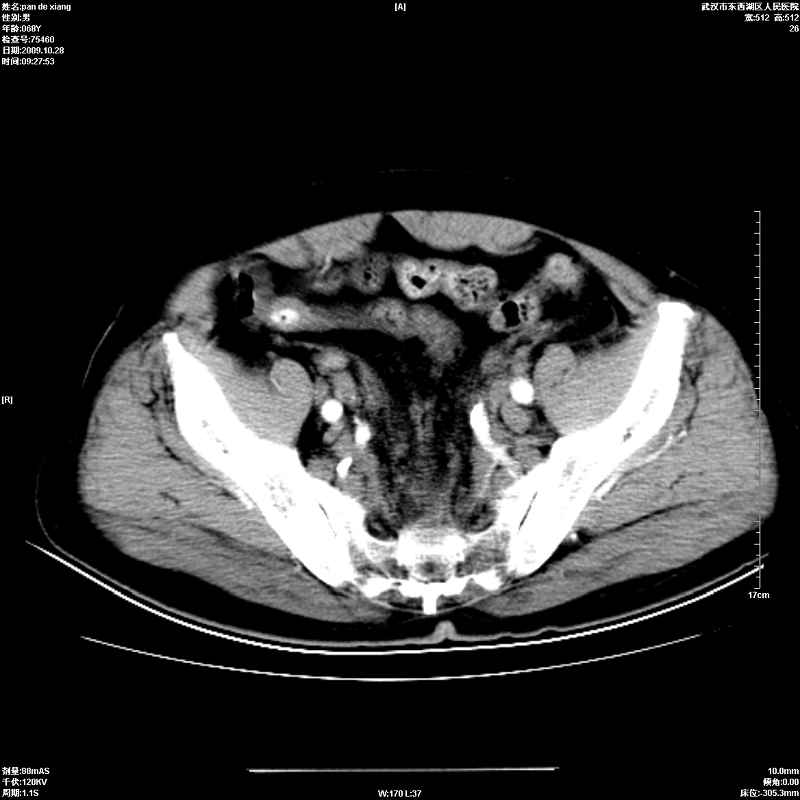

以下是引用杀毒软件在2009-10-28 20:41:00的发言:[br]结合临床考虑---白血病双肾改变或淋巴瘤。

以下是引用zxl51642在2009-10-29 9:59:00的发言:[br]结合临床“单克隆免疫球蛋白血症”,考虑双肾为继发损害并肾功能不全(尿中大量igg及少量iga、igm等大分子免疫球蛋白滤出所致继发损害),椎前软组织肿块为髓外造血。与浆细胞瘤有区别,平扫时有战友说的很清楚。